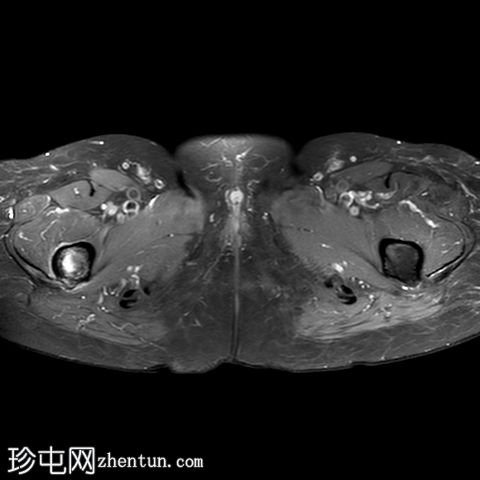

轴向PD

脂肪饱和度

一条水平T1和T2低信号骨折线横断右股骨干外侧皮质。近1/3的骨干周长受累,并伴有邻近骨髓水肿。其余皮质骨完整。左股骨未见异常。